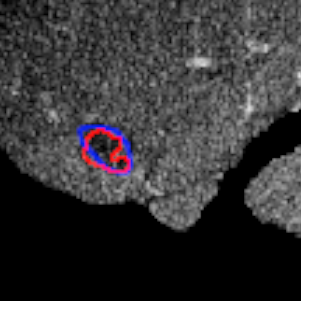

Each pixel of the image is assigned to one of the two classes liver/other tissue and tumor/other tissue, respectively, with a certain probability. Results of the automated liver and tumor segmentation are visualized in Figure 3.2. Comparison with ground truth and segmented liver and tumor give rise to the assumption that our approach is highly promising for obtaining high performance metrics. To qualitatively evaluate performance, we applied some of the commonly used evaluation metrics in semantic image segmentation. Performance metrics are summarized in Table 1.

Area under ROC Curve (AUC) is a performance metric for binary classification problems. We applied ROC analysis to find the threshold that achieves the best results for the tumor segmentation task. Due to the very low rate of false classified pixels (most of them has probability close to one or close to zero), we decided to restrict the ROC curve to pixels whose probability for belonging to class tumor lies between 0.01 and 0.99.

In Figure 3.4 we can see that the best restricted AUC value (rAUC) conducting is achieved by a very small value of . We further calculated the corresponding threshold and could achieve an improvement of the tumor segmentation results [7].